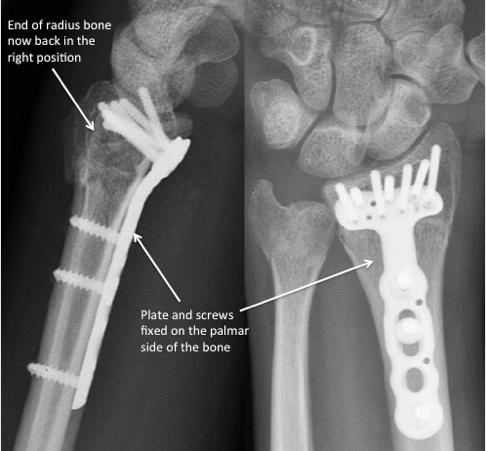

There are many ways to surgically restore the position of the fragments, and stabilise them while the fracture heals. In the majority of cases, specialist wrist surgeons will use a form of plate and screws specifically designed to be fixed to the palmar aspect of the bone, through an incision of around three inches:

Plate and screws fixed to the palmar aspect of the bone